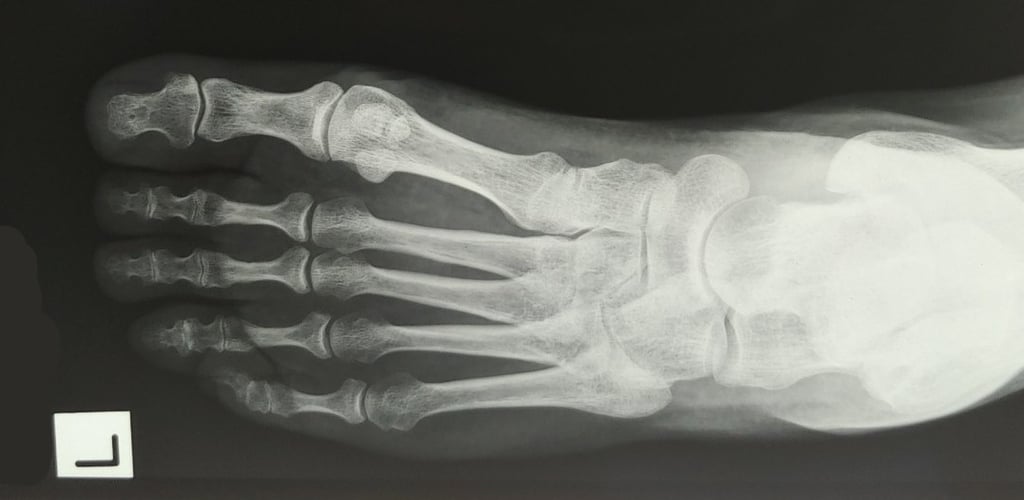

Foot